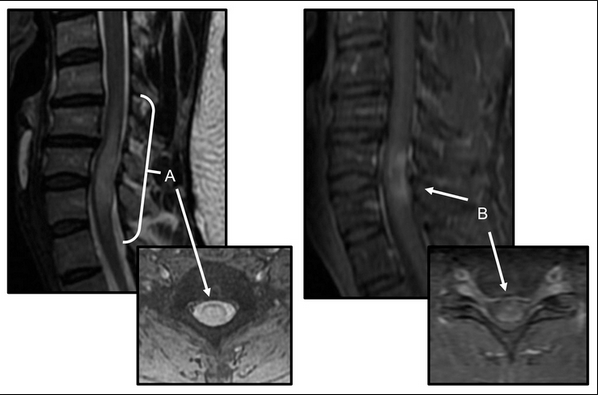

The av shunt is located inside the dura mater close to the spinal nerve root where the arterial blood from a. They most commonly affect elderly men and are classically found in the thoracolumbar region. As part of a health sciences university, baylor medicine in houston, texas puts the latest treatments, innovations, and therapies in the hands of its highly trained doctors and care teams, who are working together to develop and deliver a care plan personalized for you. Compression of the upper spinal cord, multiple sclerosis, transverse myelitis, behçet's disease, osteogenesis imperfecta lhermitte phenomenon , also called the barber chair phenomenon , is an uncomfortable electrical sensation that runs through the back and into the limbs. In the acute setting, there is often associated contrast enhancement. Transverse myelitis postsurgical spine avm brachial plexus post radiation therapy, eval for mass lesions, entrapment, denervation cervical spine w and w/o contrast 72156 thoracic disc disease pain radiculopathy trauma thoracic spine w/o contrast 72146 tumor infection ms syrinx transverse myelitis postsurgical spine avm Rare neurological complications include transverse myelitis and/or cauda equina syndrome 20, 21; Jan 14, 2017 · transverse myelitis is an inflammatory condition of the spinal cord associated with rapidly progressive neurologic dysfunction.